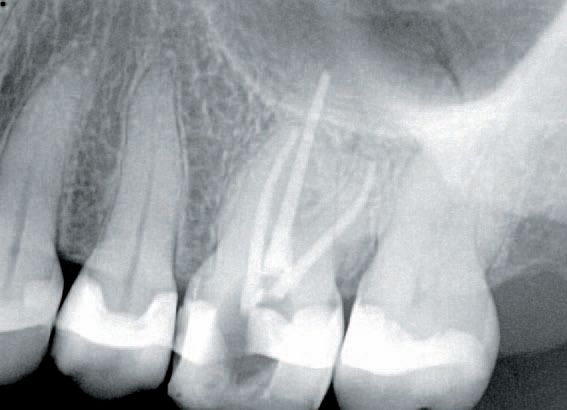

Case two: Maxillary left second bicuspid

The patient presented with temperature sensitivity and pain during mastication. The treatment plan consisted of endodontic therapy on tooth No. 13 to be followed up with post and core treatment and an IPS e.max® CEREC® crown.